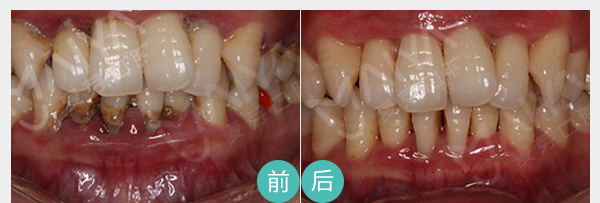

麦芽EMS洁牙将超声波洁牙、喷砂洗牙双重洗牙技术二合一,30分钟给你舒适的体验,清洁口内牙菌斑及其附着的牙结石。

适应症:牙周炎